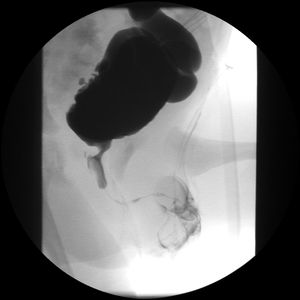

초음파 영상 검사는 방광의 모양, 배뇨 후 잔뇨량, 신장 크기, 두께 또는 요관 확장과 같은 신장 손상 증거에 대한 정보를 제공할 수 있다.[8] 초음파에서 방광 벽 비후는 수신증 및 결석과 같은 요로 이상이 발생할 위험이 높다는 것을 나타낸다.[9] 배뇨 방광요도조영술 검사는 조영제를 사용하여 방광이 가득 찼을 때와 배뇨 후의 영상을 얻으며, 이는 신경인성 방광과 일치하는 방광 모양의 변화를 보여줄 수 있다.[8]